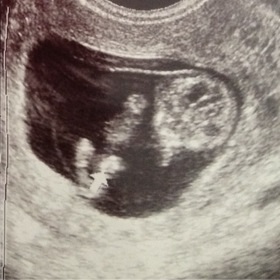

8週目に出血をして切迫流産になり、安静後初めての内診。 内診中に足を伸したり、手を伸す姿が見えて感動しました。

手をウネウネ動かして楽しそう♪ 心拍も確認できました!